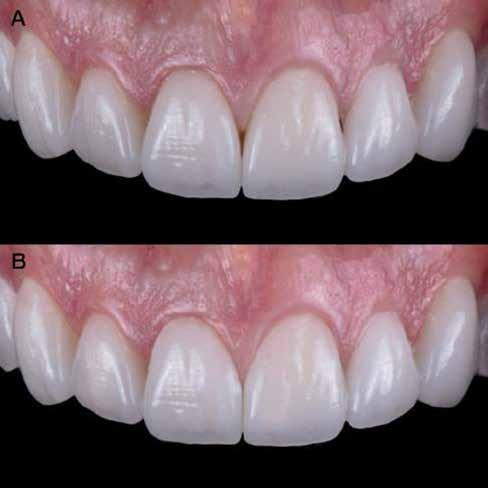

Az oxigén inhibíciós réteg kialakulásának elkerülése érdekében a kerámiafelszíneket glicerin géllel (Liquid Strip, Ivoclar Vivadent, Schaan, Liechtenstein) borítottuk, majd ezeket a felszíneket ismét 20-20 másodpercen keresztül világítottuk. A végeredmény megfelelt a páciens esztétikai igényeinek (6. a. ábra). Az átadott restaurátumok épségének megőrzése érdekében, a páciens számára éjszakai fogvédő sín készült. Az ötéves kontroll alkalmával megállapítottuk, hogy az elvégzett kezelésünk továbbra is sikeresnek tekinthető (6. b. ábra)

Az általunk alkalmazott adhezív rendszerek hatékonyságát nagymértékben növelhetjük azáltal, hogy a fogakat minimál invazív módon, azaz csak zománcon belül preparáljuk, és a kerámia héjakat kofferdám izolálásban ragasztjuk. Jelen esetismertetésünknek az volt a célja, hogy bemutassuk, hogyan lehet az adekvát módon kivitelezett kofferdám izolálással megelőzni

a munkaterület nyállal, vérrel vagy szulkusz-váladékkal történő kontaminációját. A megfelelő méretben kialakított perforációs nyílások és köztük lévő optimális távolság elengedhetetlen ahhoz, hogy a kofferdámot ideális módon tudjuk felhelyezni. Ezzel az esettel azt is bizonyítjuk, hogy a gumilepedő levegőfújással, fogselyemmel és teflonszalagok segítségével történő beforgatásával az ínyvérzés kialakulását el lehet kerülni. Ismételten szeretnénk hangsúlyozni, hogy a megfelelő kofferdám kapcsok használata nélkül nem tudtuk volna a preparált csonkszélt a gumilepedő szélétől eltartani. A kezelés során elért eredményeket jól alátámasztotta, hogy a páciens az ötéves kontroll vizsgálat során teljesen elégedett volt.

A páciens elégedett volt a végleges restaurátumok színével, formájával és méretével. A kezelés végeredménye kielégítette az esztétikai elvárásait (9. ábra). A frissen átadott restaurátumok épségének megőrzése érdekében a páciens számára éjszakai fogvédősínt készítettünk. A páciensünk a négyéves kontrollvizsgálat során is nagyon elégedett volt a kezelés eredményével. A korábban meglévő fekete háromszögek eltűnésének különösképpen örült (9. és 10. ábrák)

9. ábra. A beavatkozás után, valamint a 4 évvel később látható állapot. (A): Egy héttel a ragasztás után készült felvétel. (B): A négyéves kontroll alkalmával készült felvétel.